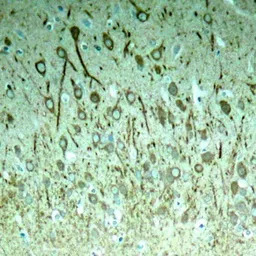

IHC-P analysis of rat hippocampal region tissue from a model with Alzheimer using GTX50174 Tau (phospho Thr231) antibody.